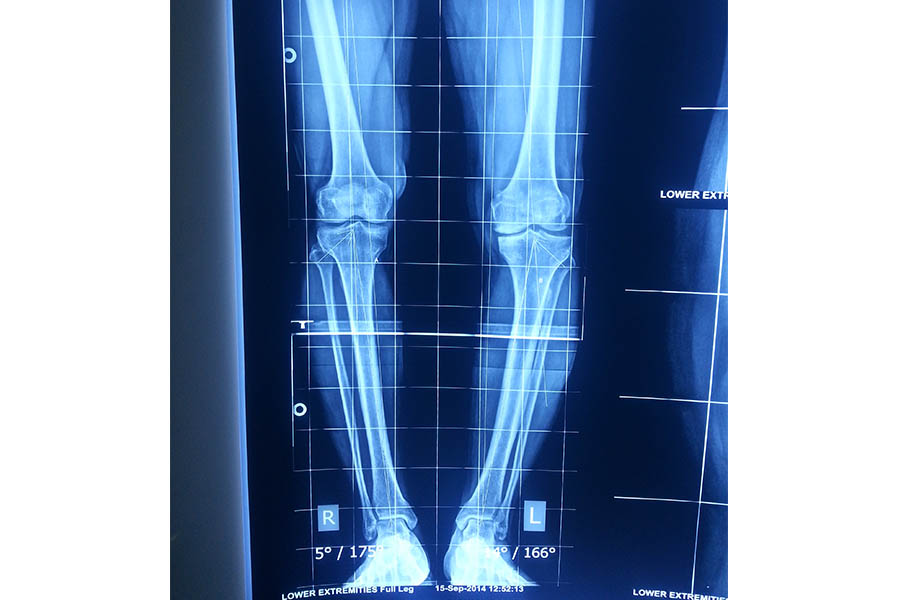

Trauma